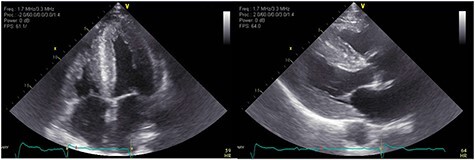

An 83-year-old white male presented with nonexertional chest discomfort, easy bruising and bleeding. His PMH was notable for HLD, OSA, CKD-IV, permanent AFib, sick sinus syndrome, CHF, CAD s/p CABG. Mildly elevated TnI at 0.10 ng/ml and elevated NT-proBNP at 10700 pg/ml was noted. EKG showed AFib and LQRSV. TTE resembled infiltrative cardiomyopathy (Fig. 7). Holter monitor showed a significant premature ventricular contraction (PVC) burden (>24 000 PVC’s/day, or 41%). The nuclear stress test, Tc99-PYP and genetic analysis were nonrevealing (Fig. 8). Left lung upper lobe wedge biopsy was positive for amyloidosis (Fig. 5).

Figure 7 .

TTE showing moderate concentric LVH, severe left atrial enlargement.

Figure 8 .

Technetium PYP scan was equivocal with patchy PYP uptake.

A 73-year-old African-American female presented with worsening DOE, peripheral edema, worsening peripheral neuropathy (PN). Her PMH was notable for type-1 diabetes mellitus, hypothyroidism, OSA, HTN, hyperlipidemia (HLD), coronary artery disease status post coronary artery bypass grafting (CAD S/P CABG), PN, CTS. Her sister passed away from ATTR-CA. TTE was suggestive of infiltrative cardiomyopathy (Fig. 6). CMR and Tc99-PYP scan were nondiagnostic. Genetic testing for saliva was positive for pathogenic mutation PV 142I heterozygous, suggestive of ATTRm-CA.

Figure 6 .

TTE showing increased echogenicity in the ventricular septum.